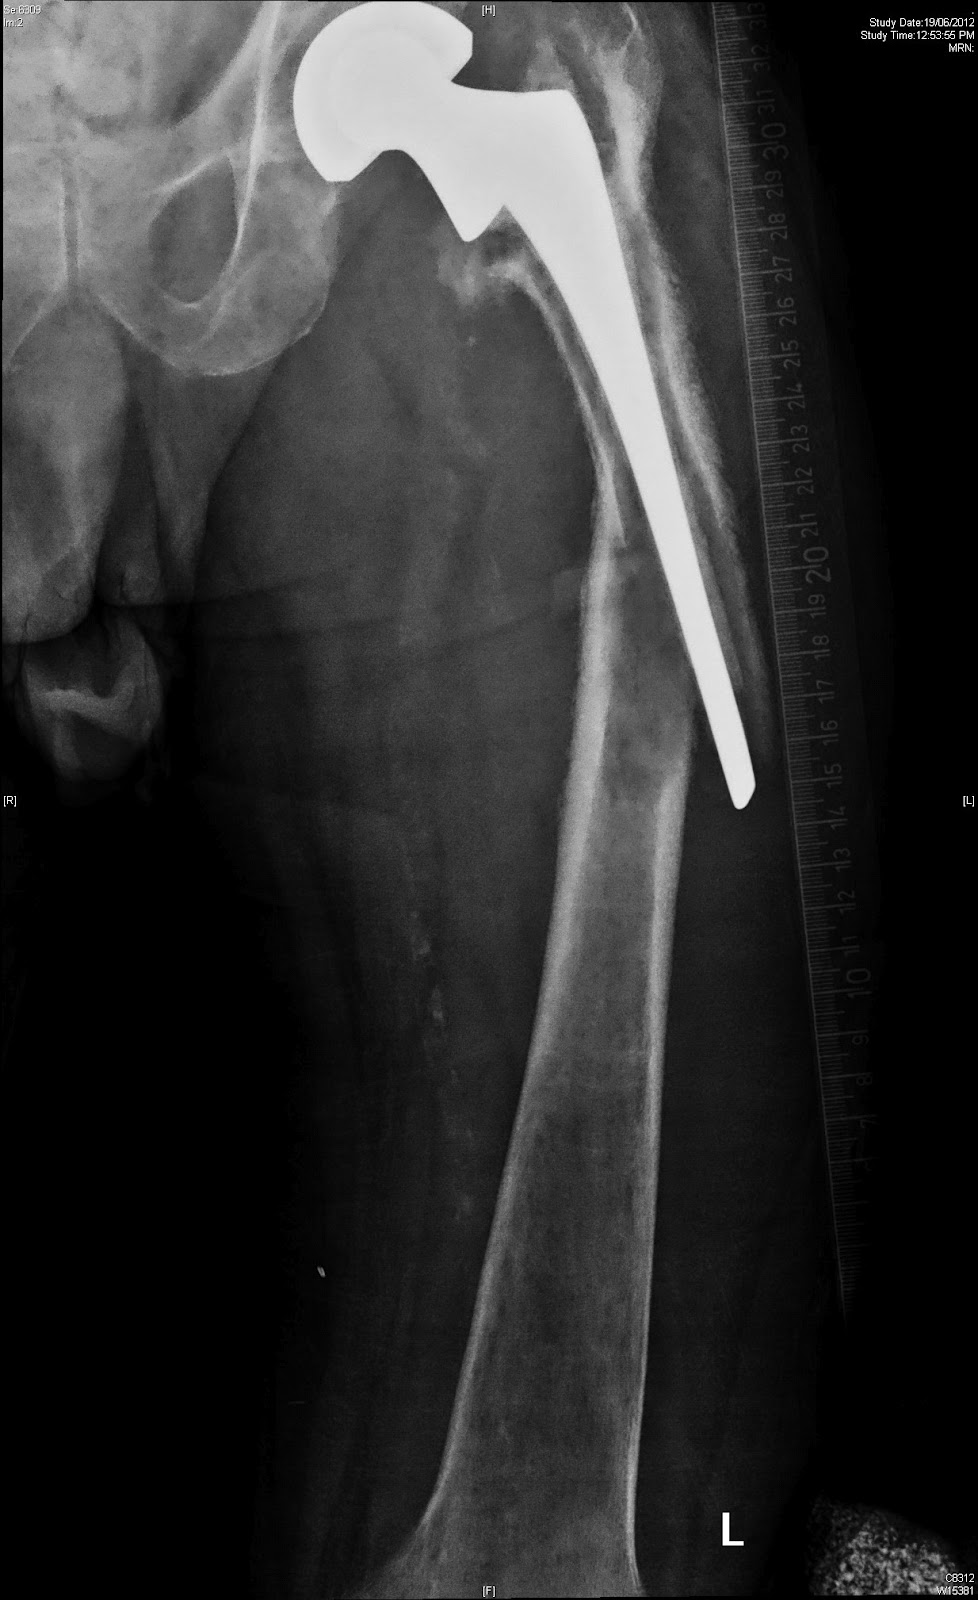

TKA Periprosthetic Fracture - Recon - Orthobullets from upload.orthobullets.com

Doi fractures of the distal femur, proximal tibia, and patella that occur adjacent to a total knee replacement may be very difficult. However, there has not been a reported case of periprosthetic total knee arthroplasty. Distal femoral fracture is a rare, but significant, postoperative complication of anterior cruciate ligament reconstruction.

Periprosthetic fractures around the knee. Periprosthetic fractures around the knee. Periprosthetic fracture associated with joint replacement is a common reason for revision 9. Fractures of the tibial side occur least frequently and often pose reconstructive challenges to the. Periprosthetic fractures around tka can occur both intraoperatively and postoperatively. The other hand, knee revision in periprosthetic fracture. Peroprosthetic fractures about the knee in geriatric patients. (1) the level of the fracture periprosthetic fracture is an uncommon complication post arthroplasty,54 although it is. Eng ga, rorabeck ch, eds. Keating e.m., haas g., meding j.b. Fracture neck of femur for the frcs orth. Fractures with a loose prosthesis (rorabeck iii and felix b) are best stabilised by hinged revision @article{ruchholtz2013periprostheticfa, title={periprosthetic fractures around the knee—the best. • periprosthetic fractures • comminuted fractures • supracondylar fractures • fractures in osteopenic support the knee, but allow the leg to move freely. A variety of methods has been described to stabilise periprosthetic fractures around total knee. Epidemiology of periprosthetic fracture of the femur in 32 644 primary total hip arthroplasties: Acterizing periprosthetic knee fracture patients add to. Surgeon often faced with elderly patients with complicating morbidities.